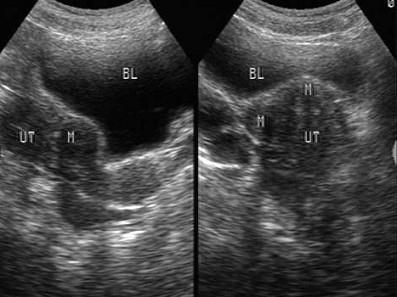

超声检查如图,最可能的诊断是 ( )A、畸胎瘤B、早孕C、子宫内膜癌D、节育器下移E、子宫肌瘤

选项 A、畸胎瘤 B、早孕 C、子宫内膜癌 D、节育器下移 E、子宫肌瘤

答案 E